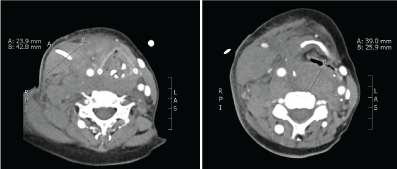

13 hours after insertion of the CVC, Heparin was re-started with a dose of 25.000 IE/24 h (= 21.7 IE/kg/h), followed by regular measurements of anti-Xa-activity. After measuring an anti-Factor Xa activity of 1.07 IU/ml five hours after the start of the heparin, the dose was reduced to 22.000 IE/24 h (= 19.1 IE/kg/h). Another five hours later (18 hours after CVC insertion), an anti-Xa of 1.66 was measured and consequently the heparin dose was reduced to 15.000 IE/24 h (13 IE/kg/h) after receiving the results followed by a still elevated anti-Xa activity of 1.05 IU/ml in the evening of day 2, 36 hours after insertion of the CVC. The dose was again reduced (12.000 IE/24 h). Around 6 hours later (42 hours after CVC insertion), the patient presented with difficulties swallowing and increasing respiratory distress. Clinical examination revealed an enormous swelling of the right-sided neck of about 8 cm × 5 cm. A CT scan of the head and neck was conducted and demonstrated a massive hematoma in the region of the sternocleidomastoid muscle, in the supraclavicular region and in the retropharyngeal space, with compression and displacement of the larynx (Figure 3). By means of an angiography, a small side branch of the thyrocervical artery was identified as a possible source the bleeding (Figure 2). Based on the artery's extremely small diameter, neither surgical nor angiographic intervention appeared as a clinical option.

Figure 3: Contrast-enhanced CT images of the neck demonstrating the large hematoma in the sternocleidomastoid muscle (left) and in the retropharyngeal space (right). View Figure 3